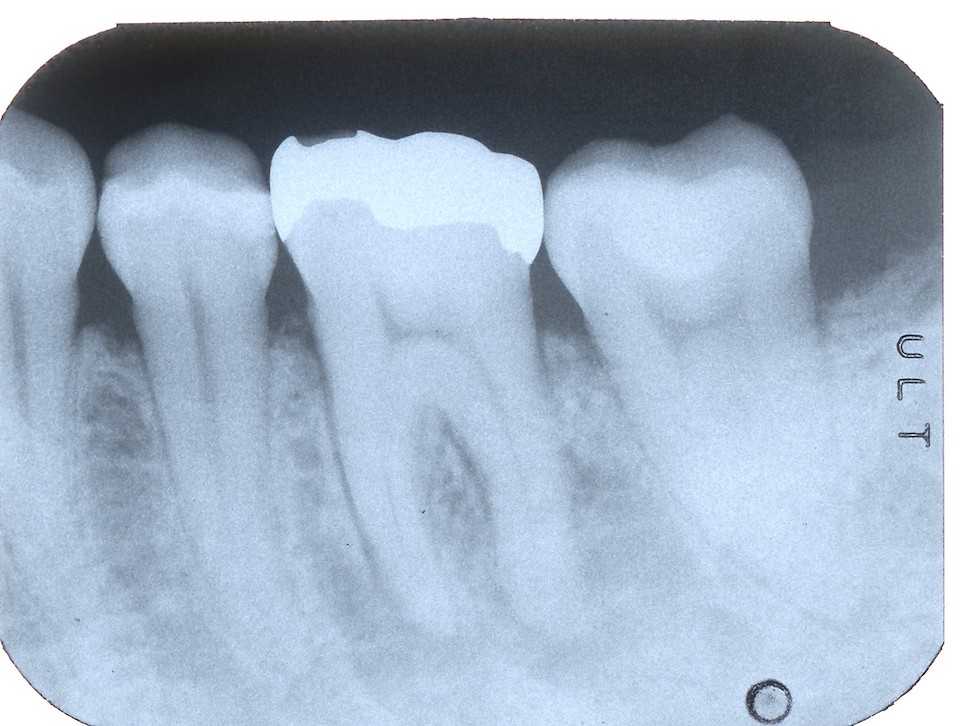

40台女性、左下6、Per、外傷性クラック

GAができていたので歯髄を開けて見たのだが、クラックがあったので3MIX+α-TCPで根管充填したが、GAは消えなかった。やはりクラックが深部まで進んでいるのか?

これ以上の打つ手がないので抜歯再植を試みた。

抜歯も分割抜歯だったがまだ病状が進んでいないので骨植もよかったので、かなり時間もかかり難しかった。

結局クラックは遠心根だけで近心根には見えなかったので、側枝があるのかもしれないが、近心のGAの原因はよく分からなかった。どうなるのか、経過観察が必要だ。

とりあえずレントゲン写真でのbefore/after

after